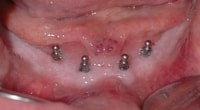

Diese Art der Sofortversorgung bedarf im Unterkiefer mindestens 4 und im Oberkiefer, aufgrund der weicheren Knochenstruktur, mindestens 6 Implantate. Von entscheidender Bedeutung ist hierbei, dass sich die Implantate stabil im Kiefer verankern lassen. Durch ihren schmalen Aufbau kann der Zahnarzt sie auch bei schwierigen Knochensituationen setzen, für die herkömmliche Implantate erst einen umfangreichen Aufbau der Knochen erforderten. Mit den Mini-Dental-Implantaten von 3M Espe schaffen wir es in ca. zwei Stunden, dass Ihre Prothese auf Dauer stabil sitzt.

Nach Ausmessung der optimalen Implantatlänge am Röntgenbild präpariert der Zahnarzt unter örtlicher Betäubung ein minimales Loch zur Aufnahme des Implantates. In der Regel ist dafür kein Schnitt notwendig. Nach dem Eindrehen des Implantates wird das Druckknopfsystem in die Prothese eingearbeitet. Der Patient kann darauf mit einer vom Zahnarzt fixierten Prothese die Zahnarztpraxis verlassen. Er sollte in den folgenden Tagen allerdings etwas weichere Nahrung zu sich nehmen.